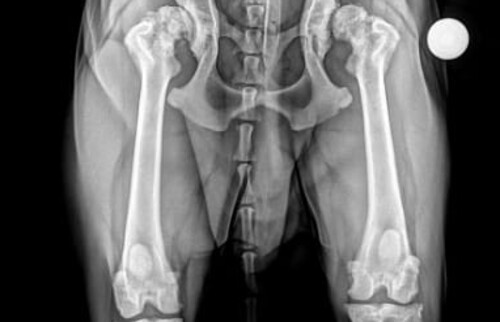

Ganz gleich, ob Hüftdysplasie beim Hund oder Hüftdysplasie bei der Katze – die Erkrankung zeigt sich oft versteckt und schleichend mit häufigem Absetzen, reduzierter Spielfreude und im späteren Stadium mit Lahmheit. Da die Erkrankung häufig beiderseitig auftritt, werden Symptome nicht selten verschleiert und sind nicht offensichtlich.

Anzeichen wie Lahmheit, eingeschränkte Beweglichkeit, Schwierigkeiten beim Aufstehen oder deutliche Schmerzreaktionen beim Laufen und Springen können auf ernsthafte Hüftprobleme hinweisen. In der Kleintierklinik Ettlingen bei Karlsruhe verhilft Dr. Lautersack mit führenden Verfahren und individuellen Behandlungsmethoden Ihrem Tier zu neuer Bewegungsfreude.

Hüftdysplasie und Arthrose bedingte Beschwerden müssen nicht das Ende von Bewegungsfreude bedeuten. Ebenso wenig traumatische Ereignisse wie die Luxation der Hüfte, die Oberschenkelhalsnekrose der Zwergrassen oder die Kopfkappenluxation der Katze (Slipped Capital Physis).Mit einem umfassenden Behandlungsspektrum gibt das Team rund um Dr. Lautersack Hunden und Katzen wertvolle Lebensqualität zurück.

Bereits im Alter von 16 Wochen kann durch eine Frühuntersuchung die künftige Entwicklung der Hüfte zuverlässig beurteilt werden. Dadurch ergeben sich wie beim Menschen frühe Therapiemöglichkeiten, die spätere schwere Schäden verhindern.